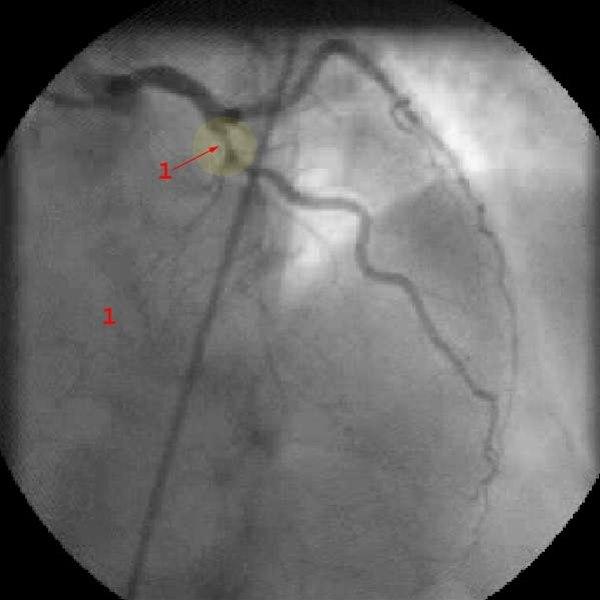

Stenose i venstre koronararteries fremre nedadstigende gren (LAD) (1)